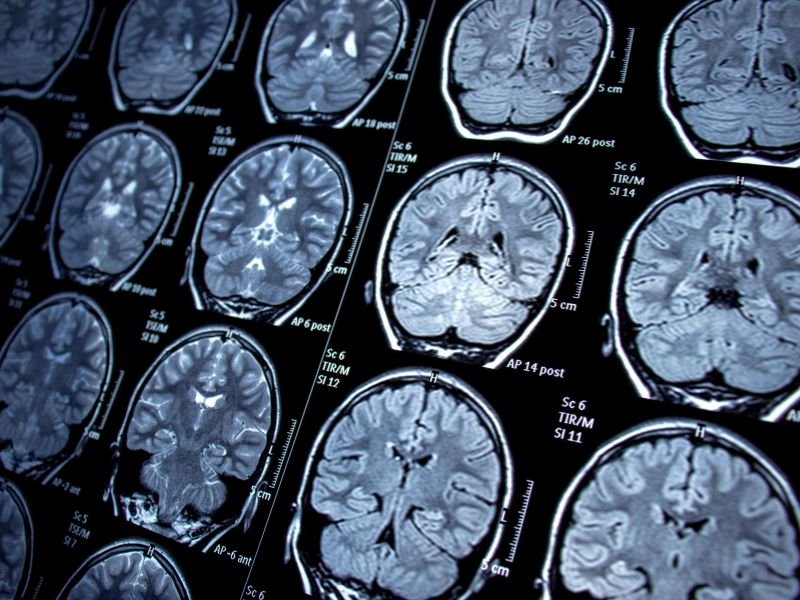

Infiltração para Dor de Cabeça em Criciúma A dor de cabeça é uma condição comum que pode afetar significativamente a qualidade de vida de uma pessoa. Em Criciúma, muitos pacientes buscam soluções para aliviar esse